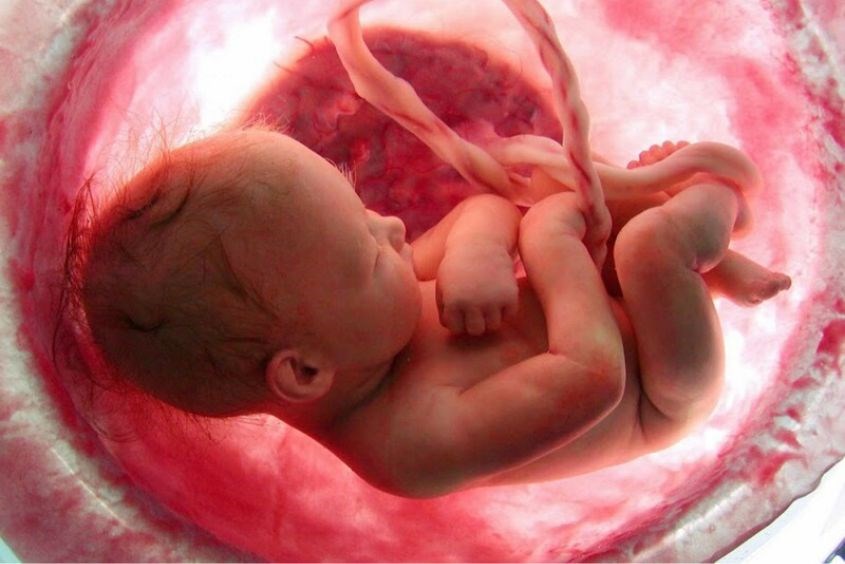

Thai nhi trong bụng mẹ sẽ được cung cấp khí oxy, các chất dinh dưỡng nhờ dây rốn. Khi dùng kỹ thuật siêu âm Doppler động mạch rốn sẽ giúp bác sĩ kiểm tra dòng chảy của máu từ nhau thai đến rốn trong các trường hợp như:

Bên cạnh đó, thông qua kỹ thuật siêu âm này có thể nhận diện thai nhi tăng trưởng chậm ở giai đoạn khởi phát sớm (trước 34 tuần).

Nếu siêu âm Doppler động mạch rốn phát hiện bất kỳ trường hợp nào khả nghi thì bác sĩ sẽ chỉ định tiếp tục khảo sát dòng máu bằng siêu âm Doppler động mạch não giữa và ống tĩnh mạch. Ống tĩnh mạch đảm nhiệm vai trò cung cấp máu giàu oxy, chất dinh dưỡng truyền đến cho não bộ và tim của thai nhi.

Như vậy, siêu âm Doppler thai là kỹ thuật siêu âm chẩn đoán hình ảnh quan trọng, giúp kiểm tra và đánh giá tình trạng sức khỏe hiện tại và mức độ phát triển của thai nhi vào các tháng cuối thai kỳ. Tóm lại, phương pháp siêu âm thai này mang đến nhiều lợi ích như